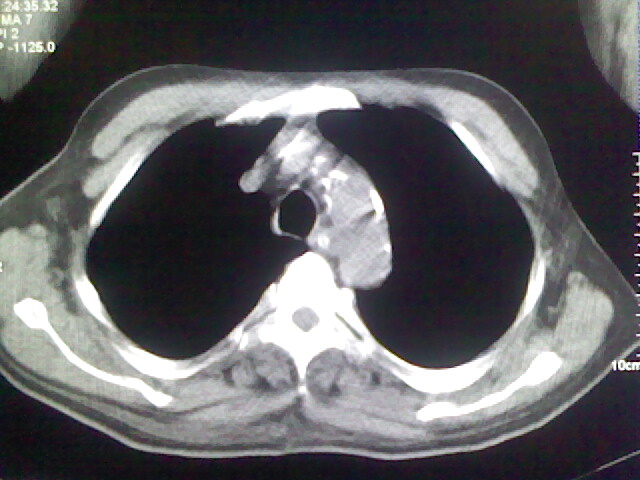

男,70岁,脑出血,长期卧床,左侧背部可触及肿块

右肺病灶考虑炎症性。

右肺病灶考虑炎症性

考虑右肺及左肺下叶炎症。

右肺及左肺下叶炎症。

考虑右肺及左肺下叶慢性炎症。

右侧肺部见片状密度增高影,边缘模糊。考虑炎症。另食管壁增厚。

右肺上叶前段病呈楔形,其尖端指向肺门,考虑肺动脉栓塞可能性大.